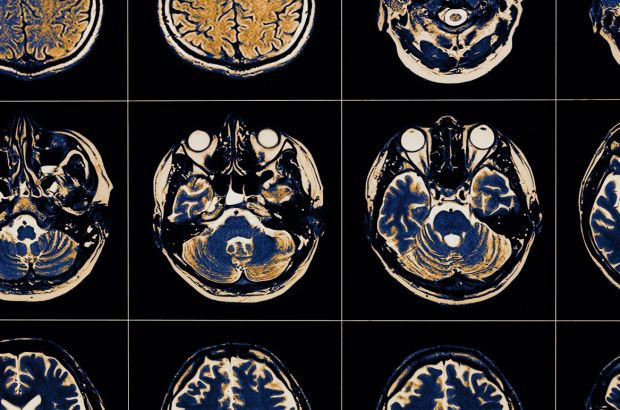

Breakthrough in Parkinson’s disease research at KU Leuven

Biomedical scientists at KU Leuven have discovered how a defect in a specific gene works to cause Parkinson’s Disease. A defect in the ATP13A2 gene was known to be one of the causes of the disease, but it was previously not known how.

KU Leuven researchers have now discovered the gene’s function in the cell, explaining how the defect can cause Parkinson’s. Their findings have just been published in Nature.

With more than six million patients around the world, Parkinson’s disease is one of the most common neurodegenerative disorders. Some 20 genetic defects have been linked to the disease, but scientists have yet to figure out the functions involved in several of these.

It turns out that the defect in the ATP13A2 gene causes cell death by disrupting the cellular transport of polyamines. When this happens in the part of the brain that controls body movement, it can lead to Parkinson’s.